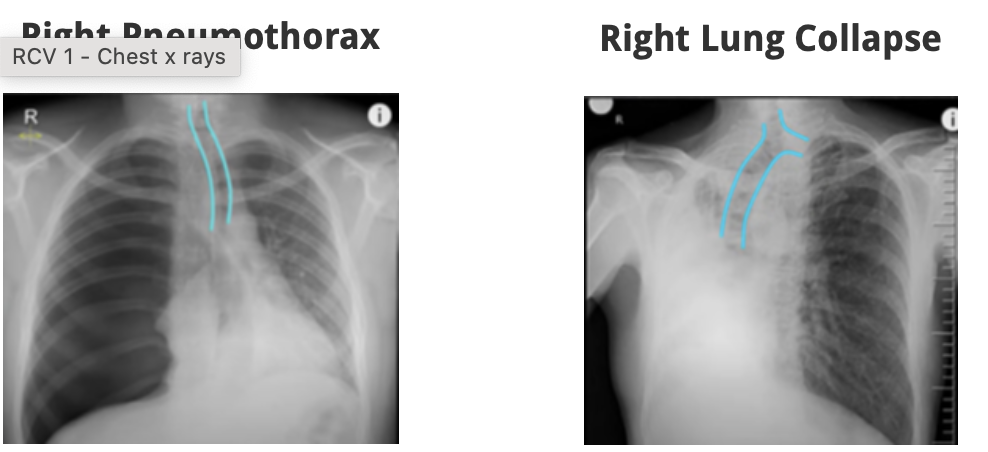

Q

-check the lung fields - compare left to right lung

-are the volumes of the lungs equal?

-are there any differences overall?